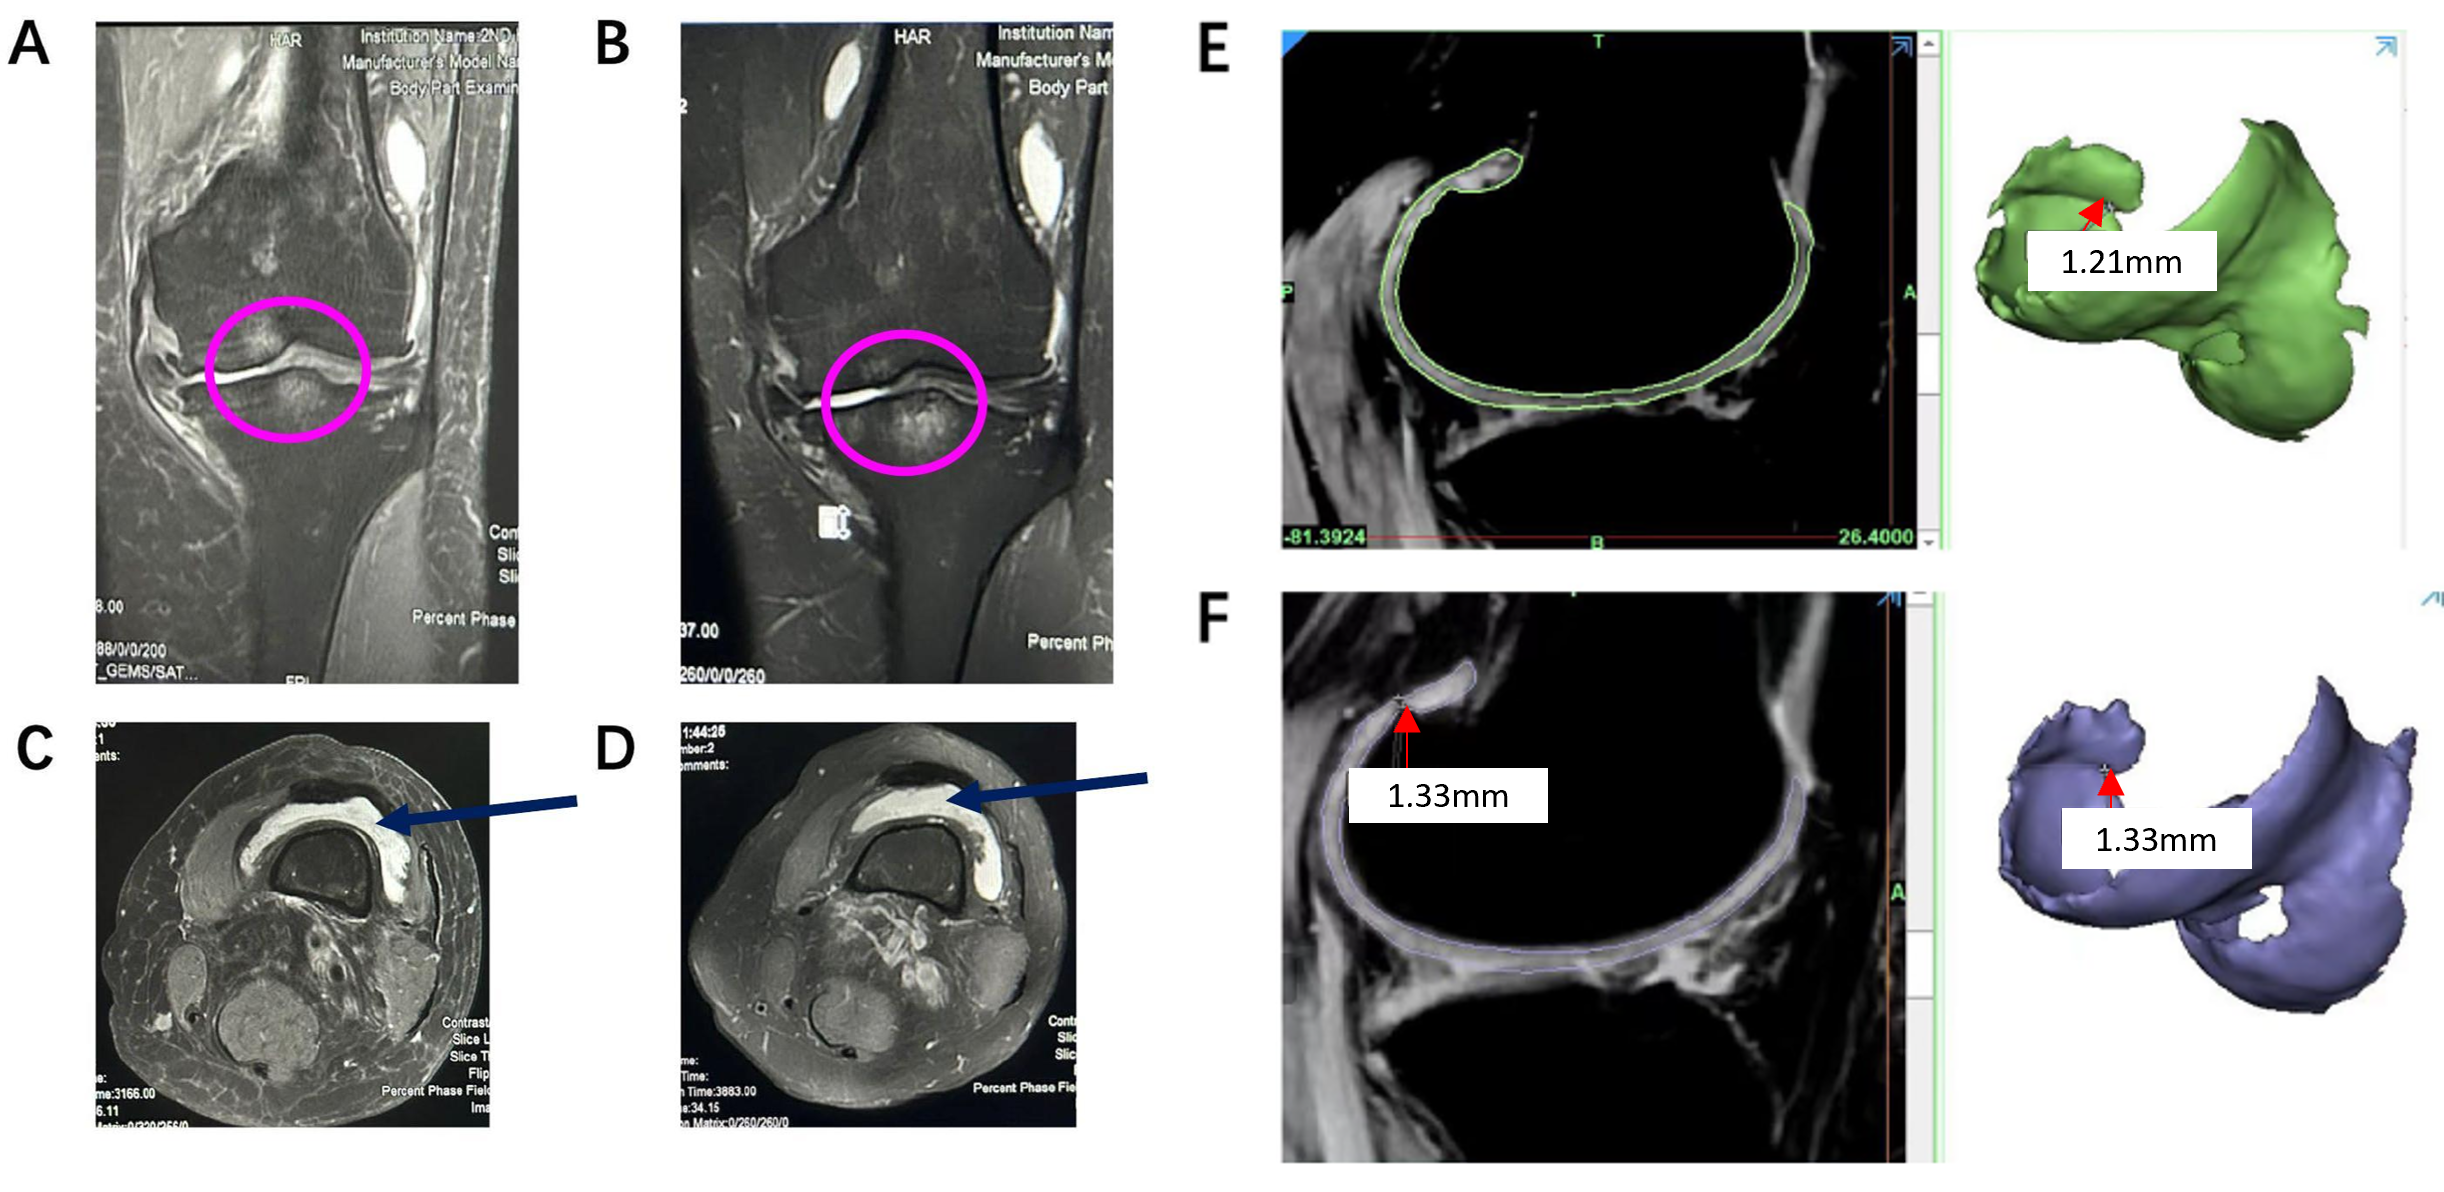

一部の患者に対し、hUC-MSCs-Exosを投与する前後でMRI検査が行われました。その結果、投与後には膝関節の腫れ(A,Bピンクの丸部分)や関節液の量(C,D紺の矢印部)が減少し、炎症の軽減が確認されました。さらに軟骨を抽出した画像解析では、軟骨の厚みがわずかに増加する変化も観察されました(E,F)。これらの結果は、hUC-MSCs-Exos投与が変形性膝関節症の症状の進行を抑えることを示唆しています。